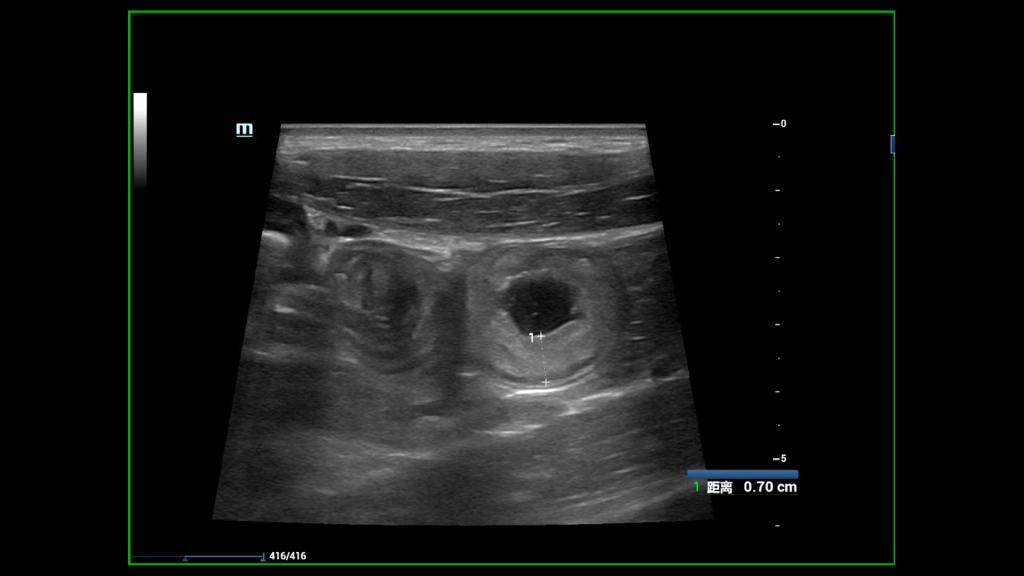

8月22日上午8时许,患儿及家属按约抵达。在超声科儿科亚专业组全体医师的参与下,由超声科刘灿主治医师负责为患儿做了详细的肠道超声检查,对整个肠道每段每节进行测量及记录,为患儿进一步治疗提供真实可靠的超声数据,解除了患儿家长的后顾之忧,患儿本人及家属十分感激,展现出灿烂的笑容。

随着医学水平不断发展,CD的治疗目标已经从症状缓解转变为黏膜愈合。将“全壁愈合”作为CD更深层次的治疗目标。CD “全壁愈合”可以通过磁共振小肠造影 (MRE)、计算机断层扫描 (CT) 和肠道超声 (IUS)进行评估。肠道超声 (IUS)可以检测CD疾病活动、病变范围和并发症,具有非侵入、无创无辐射、易于重复且成本低的优点,尤其适用于小儿。因此,将肠道超声作为判断CD“全壁愈合”的标准,逐渐受到越来越多的关注。